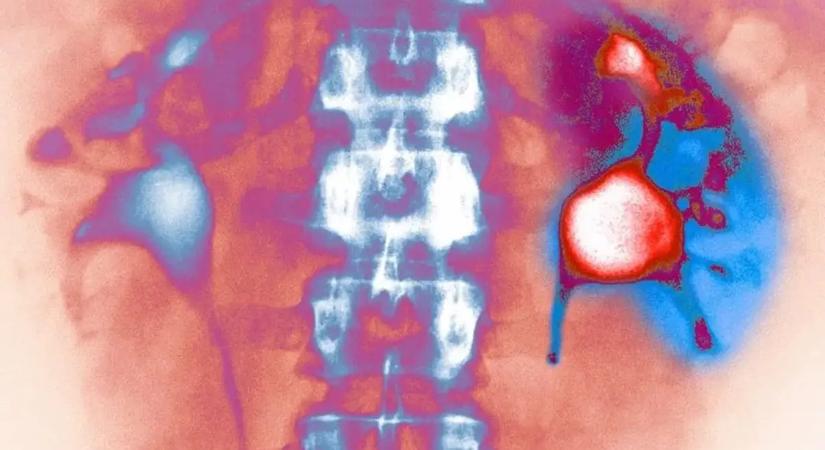

A több víz ivása sem óv meg a vesekő kiújulásától

Évtizedek óta az orvosok egyetlen fő tanácsot adnak a vesekő megelőzésére: igyunk több vizet.